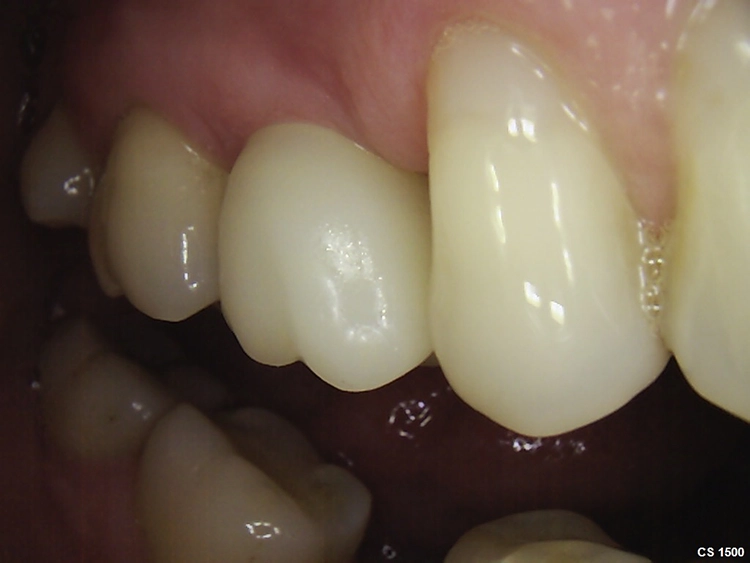

Abb. 2: Repräsentativer Fall von ABH Grad B Septus Typ II. a) Ansichten vor der Installation. Röntgenaufnahme der periapikalen Läsion an einem wurzelkanalbehandelten Molaren und klinische Ansicht der Typ-II-Socket nach der Extraktion. b) Die Ansichten nach der Installation zeigen das Implantat innerhalb des interradikulären Septums und das über dem Implantat platzierte A-PRF. c) Nachuntersuchungen nach 10 Tagen bzw. 2,1 Monaten. Die Röntgenaufnahme zeigt die Knochenbildung zwischen der Sinusmembran und dem apikalen Teil des Implantats. d) Jüngste Nachuntersuchung nach Einsetzen der Prothese.

Abb. 3: Repräsentativer Fall von Grad A Typ I. a) Präoperative Ansicht. Röntgenbild der periapikalen Läsion an einem wurzelkanalbehandelten Molaren. Die Höhe des Alveolarknochens zeigt Grad A an. b) Klinische und radiographische Ansicht der Implantatinsertion unter Verwendung einer Einheilscheibe mit großem Durchmesser (6×8 mm). A-PRF wurde um das Implantat und unter der Scheibe platziert. c) Nachuntersuchung nach 5,9 Monaten vor und nach der Zementierung und Aufbereitung. d) Jüngste Nachuntersuchung nach Einsetzen der Prothese

Die SDS-Zirkoniumdioxidimplantate wurden mit zementierten Pfosten weiter aufbereitet (Abb. 1d, 3 und 4c) und nach 4,74 + 0,95 Monaten Einheilzeit mit endgültigen Kronen versorgt. Die Balkonform ermöglichte ein natürliches Emergenzprofil, das die definitiven Kronen wie die Standardform ausrichtete sowie die Gesundheit des Weichgewebes und die Osseointegration förderte. Bei jeder Nachuntersuchung wurden Stabilität des Implantats, Zustand des umgebenden Gewebes und Vorhandensein von Zahnstein beurteilt.